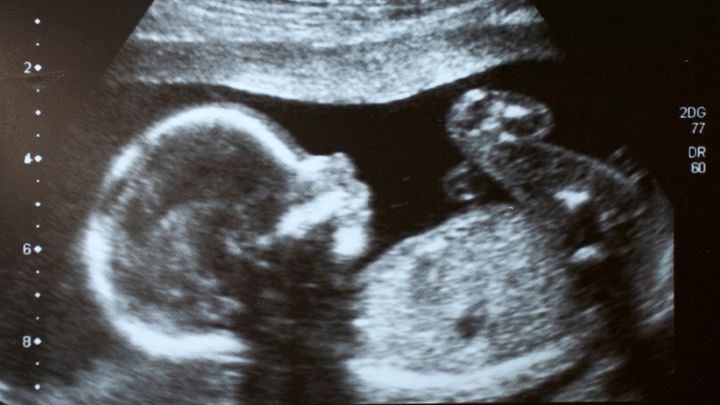

生まれる前に意識はあるのか?長年の謎に迫る「意識の種」を調査

生まれる前に意識はあるのか?長年の謎に迫る「意識の種」を調査 / Credit:Canva